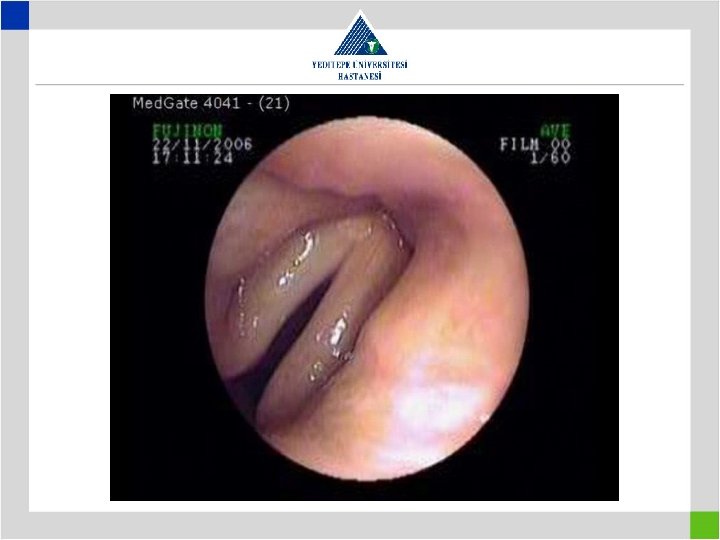

Diagnosis • Preop glottic insufficiency to be searched – Preop awake laryngoscopy – Preop work-up for presence of aspiration – Tracheostomy means previous intubation – look for a distal second lesion – Vocal cords do not move both in paralysis and cricoarythenoid arthritis or traumatic ankylosis